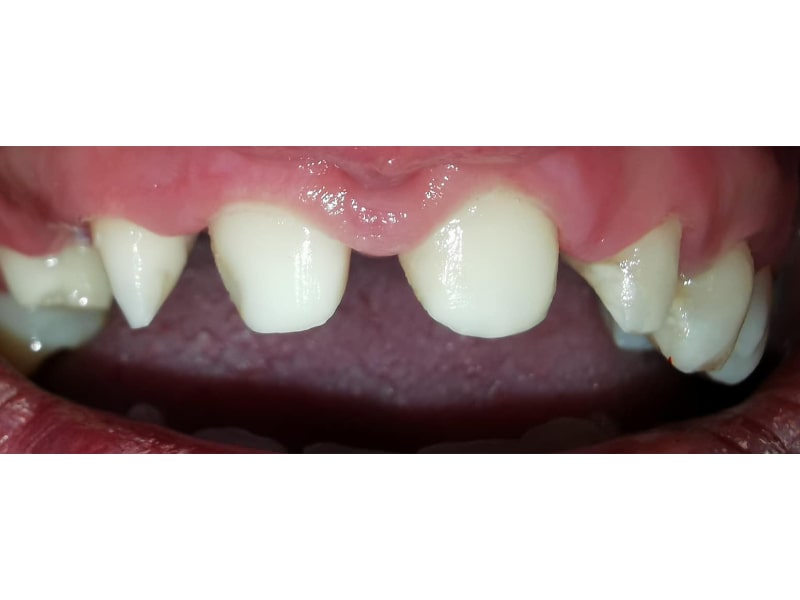

Punte Ceramică